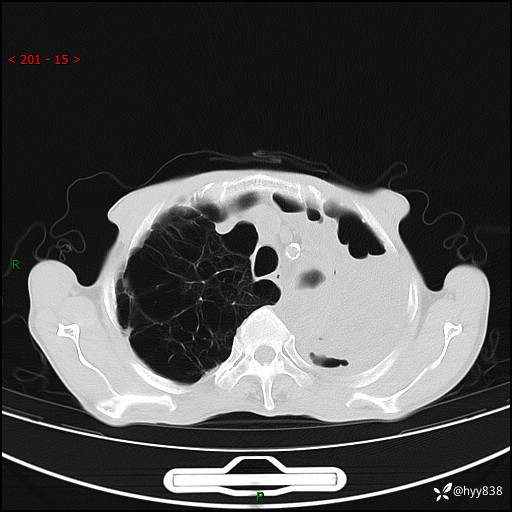

老年男性,反复咳嗽、咳痰、气喘10余年,再发3天。大叶性实变+胸膜病变-结果公布

胸部CT平扫+增强